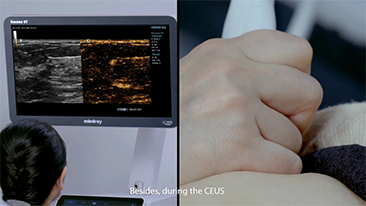

Ultrasound contrast imaging plays a significant role in identifying focal liver lesions, such as hemangioma or liver cancer.

Ultra-wide non-linear UWN+ contrast imaging technology provides better penetration, higher contrast-tissue ratio, with lower MI and longer perfusion time observation.